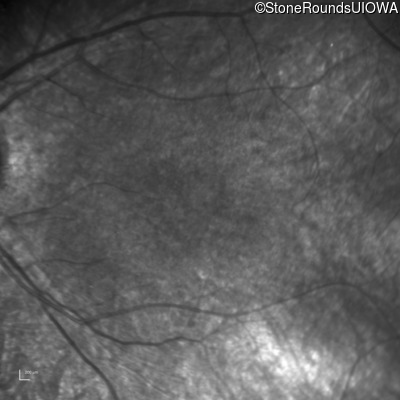

Infrared Fundus Photograph - Right - 20/100

Exemplar